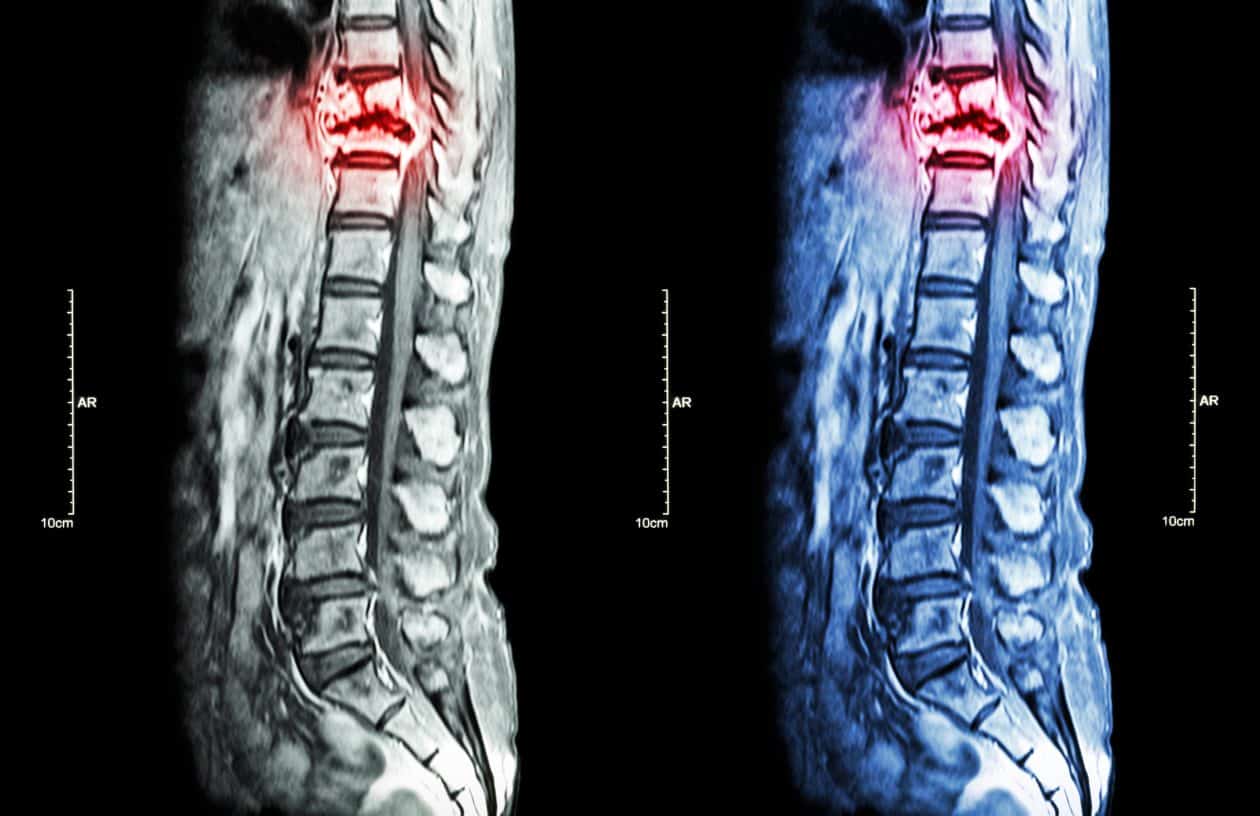

La médula espinal es una estructura vital del sistema nervioso central que se extiende desde la base del cerebro hasta la región lumbar de la columna vertebral. Las lesiones en la médula espinal pueden tener diversos efectos en la función y movilidad del cuerpo, y se clasifican en diferentes tipos según su localización y severidad.

5. Fracturas vertebrales: Las fracturas en las vértebras pueden dañar la médula espinal si los fragmentos óseos se desplazan y comprimen la estructura. Dependiendo de la ubicación y gravedad de la fractura, pueden ocurrir lesiones de diferentes tipos.

6. Hernias de disco: Los discos intervertebrales pueden desplazarse y ejercer presión sobre la médula espinal o sus nervios. Esto puede causar dolor y afectar la función neurológica.

7. Compresión medular: La compresión de la médula espinal puede ser causada por tumores, abscesos, hematomas u otras condiciones médicas. La compresión impide la transmisión adecuada de los impulsos nerviosos y puede provocar déficits neurológicos.